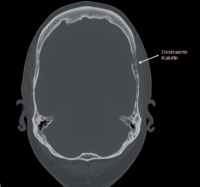

Anhand zweier Fallbeispiele wird illustriert, wie moderne Gliomchirurgie mit Neuronavigation, fluoreszenz-gestützter Resektion, intraoperativem Neuromonitoring, intraoperativer Magnetresonanztomographie und anderen Verfahren am Bundeswehrkrankenhaus Ulm umgesetzt wird.

Gliome sind die häufigsten hirneigenen Tumore [13]. Sie werden nach WHO in Grad I bis IV eingeteilt und von benigne bis maligne graduiert [10]. Die WHO Grad I-Gliome, insbesondere das pilozytische Astrozytom, weisen eine gute Abgrenzbarkeit auf. Die Patienten haben bei vollständiger Resektion meist eine normale Lebenserwartung.

Die diffus infiltrativ wachsenden Gliome (WHO Grad II – IV) hingegen haben eine reduzierte Abgrenzbarkeit und resultieren in einer deutlich geringeren Lebenserwartung für die Patienten [12]. Das Glioblastom (WHO Grad IV) ist mit einem Anteil von 45 % aller Gliome das häufigste und hat eine mittlere Überlebensrate von 5 % nach fünf Jahren. In den letzten Jahren konnte durch die Erkenntnisse aus der Molekularbiologie die Radiochemotherapie für Patienten Glioblastomen spezifisch angepasst und durch technologische Fortschritte in der Gliomchirurgie die mediane Überlebensrate von 15 auf 20 Monate erhöht werden [6].